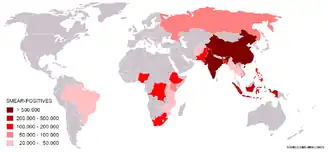

Předpokládá se, že třetina světové populace je infikována bakterií M. tuberculosis[1][7] a zhruba každou sekundu je infikován nový člověk.[1] Procento celosvětové populace, které každý rok onemocní tuberkulózou, zůstává stejné nebo klesá, ale v důsledku růstu populace se počet nakažených zvyšuje.[1] V roce 2007 bylo odhadováno na 13,7 milionů chronických aktivních případů, 9,3 milionů nových případů a 1,8 milionů úmrtí, a to většinou v rozvojových zemích.[8] Ve světě není tuberkulóza rozšířena rovnoměrně – v mnoha asijských a afrických zemích je jí nakaženo až 80 % obyvatel, kdežto ve Spojených státech jen 5–10 %.[3] V Česku bylo v roce 2023 hlášeno 459 onemocnění tuberkulózou, tj. 4,2 případu na 100 000 obyvatel,[9] v roce 2009 to bylo 710 případů, tj. 6,8 na 100 tisíc obyvatel.[10]

Bakterií M. tuberculosis je nakažena zhruba třetina světové populace a zhruba každou sekundu je infikován nový člověk.[1] Ne všechny tyto nákazy ale způsobují tuberkulózu a některé jsou asymptomatické.[63] Předpokládá se, že v roce 2007 bylo na světě zhruba 13,7 milionů lidí s aktivní formou tuberkulózy, z toho 9,3 milionů bylo nových případů. Ve stejném roce na tuberkulózu zemřelo 1,8 milionu lidí. Roční incidence se pohybovala mezi 363 případy na 100 000 lidí v Africe a 32 případy na 100 000 lidí v Americe.[8] Tuberkulóza způsobuje z infekčních onemocnění nejvíce úmrtí žen v reproduktivním věku a je jednou z hlavních příčin úmrtí u lidí s HIV/AIDS.[64]

Zvyšování počtu nákaz virem HIV a zanedbávání programů na kontrolu tuberkulózy vedly k nové vlně tohoto onemocnění.[65] Přispěl k tomu i nástup rezistentních typů tuberkulózy, kdy mezi lety 2000 a 2004 bylo 20 % případů rezistentních proti prvořadým antibiotikům a 2 % i proti druhořadým.[66] Rychlost výskytu nových onemocnění tuberkulózou se velmi liší, a to i u sousedních států, nejspíše kvůli rozdílům ve zdravotních systémech.[67]

V roce 2007 bylo státem s největší incidencí Svazijsko s 1200 případy na 100 000 lidí. Indie měla nejvíce nově nahlášených případů – 2 miliony.[8] Ve vyspělých zemích je tuberkulóza méně častá. Ve Spojeném království v roce 2007 činil národní průměr 15 nových případů na 100 000 lidí a největší míra incidence v západní Evropě byla 30/100 000 v Portugalsku a Španělsku. V Číně to pak bylo 98/100 000, v Brazílii 48/100 000 a ve Spojených státech 4/100 000.[61] V Kanadě se tuberkulóza vyskytuje v některých venkovských oblastech.[68] V Česku v roce 2007 činila incidence 9/100 000 s celkovým počtem 893 nakažených.